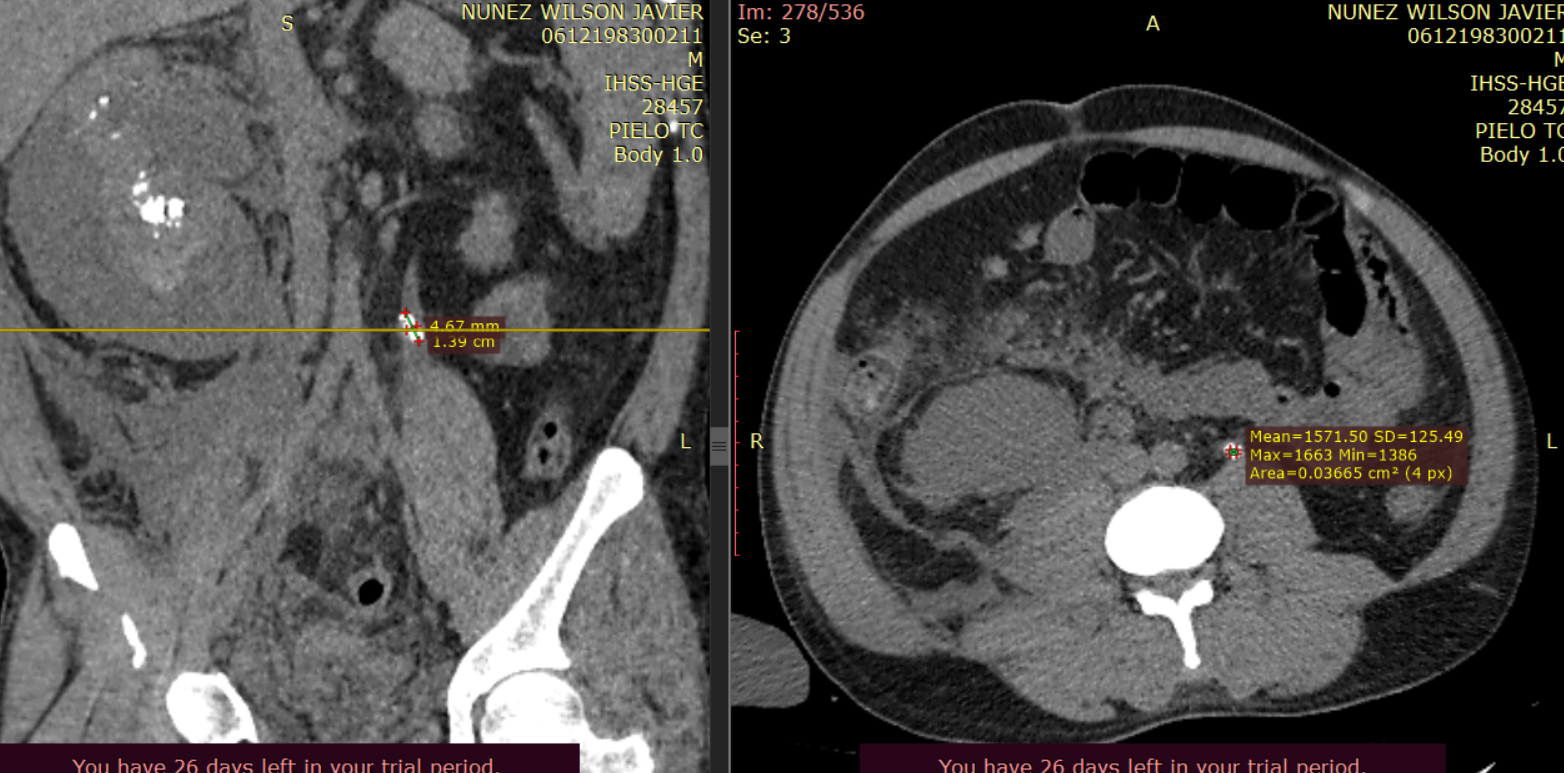

Ambos riñones se observan con presencia de imágenes hiperdensas en sitio anatómico de pirámides renales (valores de atenuación de hasta 1082UH) con presencia de colección perirrenal con densidad liquido (12UH) rodeando riñón derecho. Se observa estriación de la grasa en plano retroperitoneal derecho, extendiéndose hasta fosa iliaca derecha.

Presencia de Lito de grandes dimensiones en tercio medio de uréter derecho, con hidronefrosis secundaria. Atenuación (1500UH).

Imagen 10. Corte axial de tomografía abdominal sin contraste mostrando la presencia de imágenes hiperdensas en pirámides renales.

Imagen 10 y 11. Muestran cortes axiales a diferentes niveles demostrando la presencia de litos en tercio medio de ambos urteres.

Imagen 12 y 13. Magnificaciones de una tomografía abdominal sin contraste Demostrando la presencia de imágenes hiperdensas, dispuestas de forma difusa en pirámides renales,con presencia de colección perirrenal derecha, aumentado de tamaño.